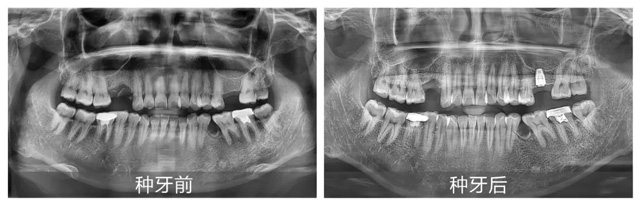

“数字化种植是新桥口腔的优势项目,无论是单颗还是全口牙种植,我们都会依据患者的口腔状况进行一对一3D数字化种植方案制定,通过使用数字化CBCT影像、3D口扫等完成术前一站式检查,有效规避后续治疗中可能存在的风险与误差。”针对今天种植直播的案例,李丹主任讲到:“我们在术前评估发现患者上颌骨量非常有限,骨高度仅为7毫米,而常规种植体至少需要8毫米的高度才能确保安全植入,为了避免可能出现的损伤,谢医生在种植手术中还需要再做一个专业、严谨的上颌窦提升手术。”

在李丹主任详细讲解的同时,手术室也已准备就绪,观众们通过实时投影,近距离见证了种植牙手术的过程。从术前消毒到定量麻醉,从精准植入再到严密缝合,谢海洋医生有条不紊地完成了每一个关键步骤,整个手术过程高效流畅。